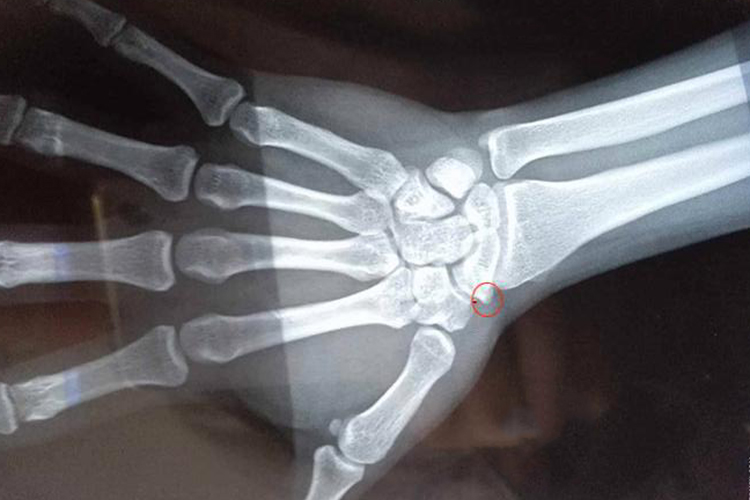

手腕骨刺是骨关节炎的一种症状,表现为手腕部疼痛、肿胀、功能障碍和畸形,X线上表现为骨质密度增高,伴或不伴有骨骼的增大。

手腕骨刺患者X线上表现为骨质密度增高,伴或不伴有骨骼的增大,骨小梁增粗、增多、密集,骨皮质增厚且致密,会有不同程度的手腕部疼痛、肿胀、功能障碍和畸形。若患者骨质增生明显,则难于分清骨皮质与骨松质。